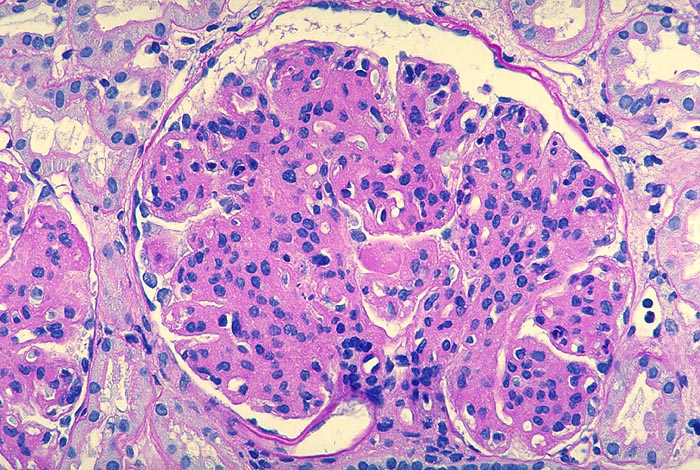

PathoPic – image database / PathoPic ID 2652 - Membranoproliferative Glomerulonephritis: lobuläre Variante

Membranoproliferative Glomerulonephritis: lobuläre Variante

Beschreibung

Phasischer Ablauf:

Initial finden sich in den Schlingen subendotheliale Immundepots begleitet von gelapptkernigen Leukozyten und Monozyten.

Mit Abnahme der endokapillären Hyperzellularität kommt es zu einer mesangialen Zellproliferation mit Auswandern der Mesangiumzellen in die Peripherie und Neubildung einer Basalmembran (mesangiale Interposition).

Schliesslich verschwinden die subendothelialen Depots, die neugebildete Basalmembran wird dicker, die Mesangiumzellzahl nimmt ab und die mesangiale Sklerose zu.

Histologie